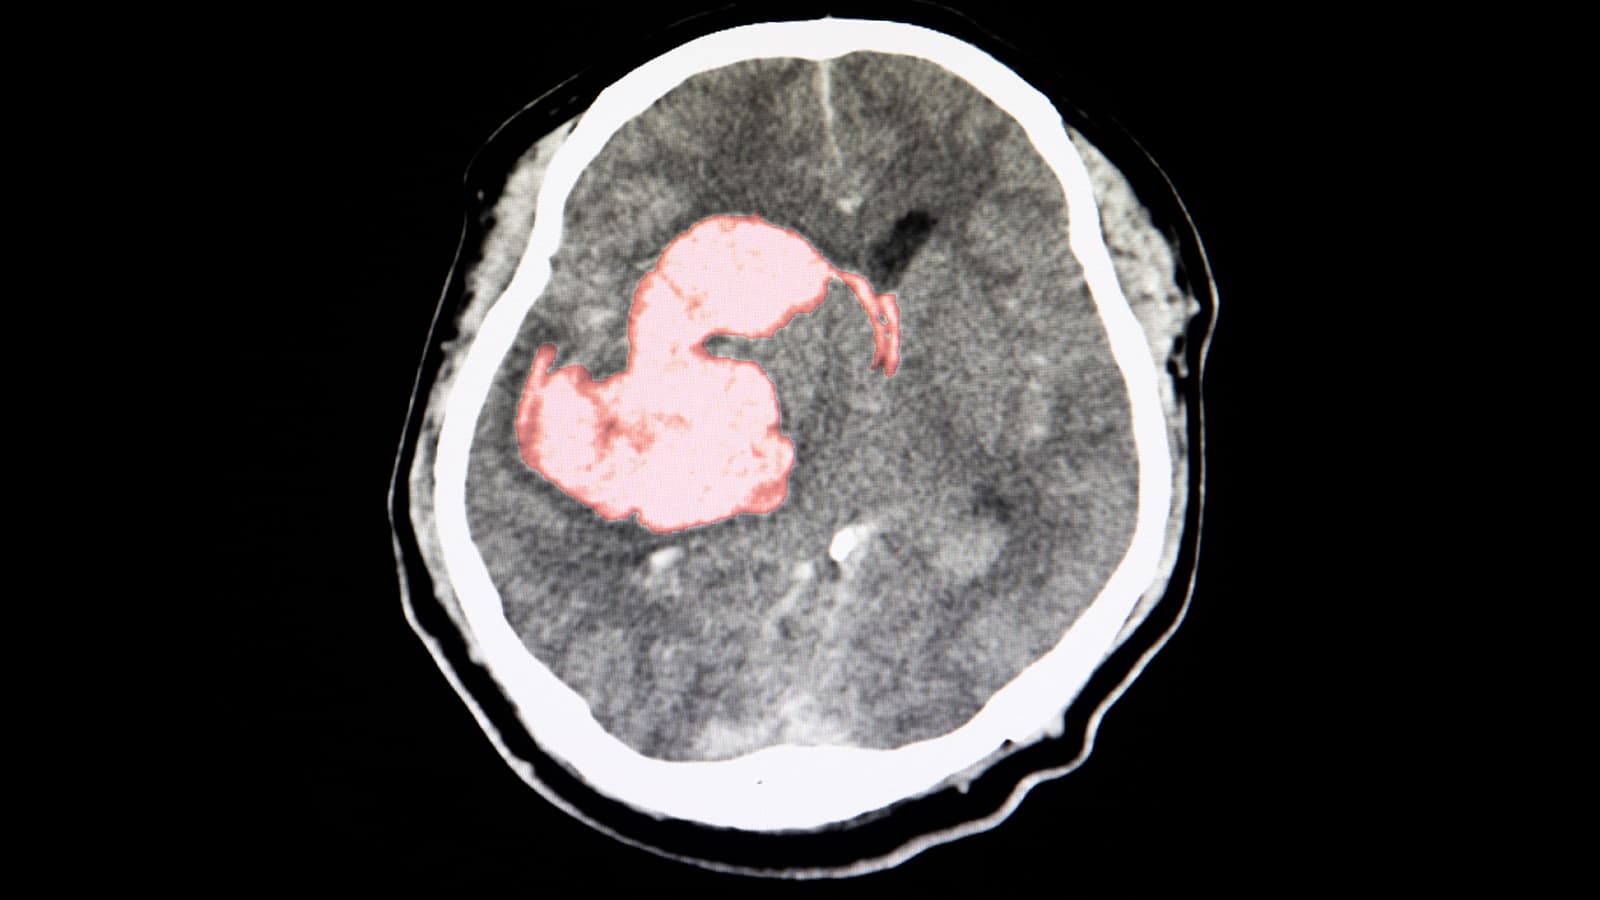

Triple Pill Gets Intracerebral Hemorrhage Survivors Closer to BP Goals

(MedPage Today) -- Additional antihypertensive treatment with a three-drug polypill benefitted patients after intracerebral hemorrhage (ICH), the placebo-controlled TRIDENT trial found. Among ICH survivors already on good background therapy randomized...